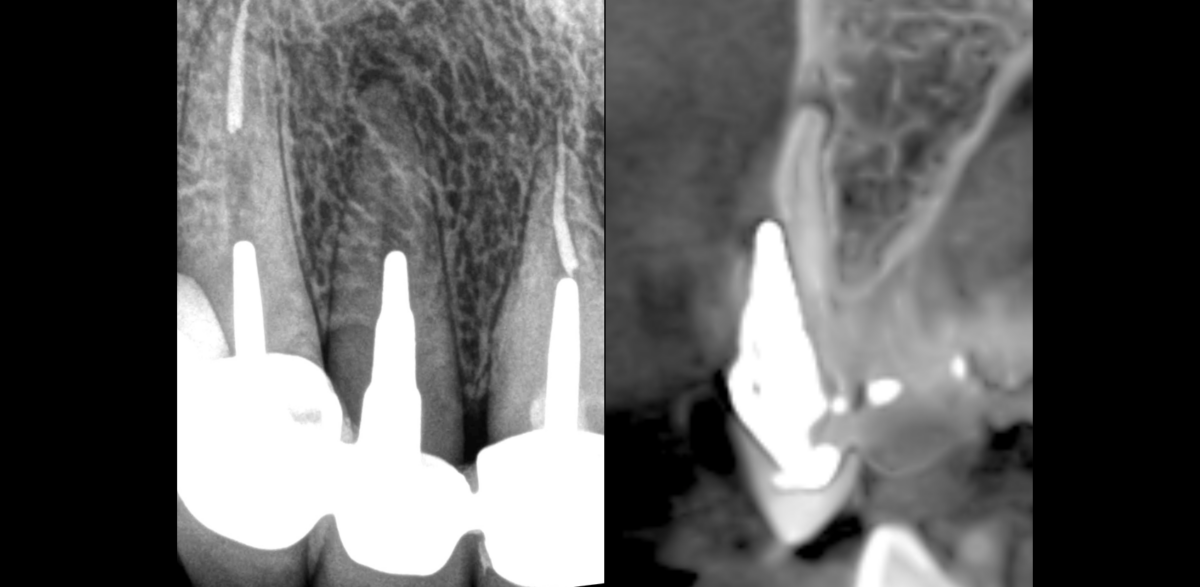

🔎 𝐒𝐭𝐫𝐚𝐭𝐞́𝐠𝐢𝐞 𝐭𝐡𝐞́𝐫𝐚𝐩𝐞𝐮𝐭𝐢𝐪𝐮𝐞 ?

✅ Profiter de la 𝐦𝐢𝐜𝐫𝐨𝐜𝐡𝐢𝐫𝐮𝐫𝐠𝐢𝐞 𝐞𝐧𝐝𝐨𝐝𝐨𝐧𝐭𝐢𝐪𝐮𝐞 pour traiter la perforation.

🦷 𝐌𝐞̂𝐦𝐞 𝐛𝐢𝐨𝐦𝐚𝐭𝐞́𝐫𝐢𝐚𝐮 𝐝’𝐨𝐛𝐭𝐮𝐫𝐚𝐭𝐢𝐨𝐧 pour 𝟐 𝐢𝐧𝐝𝐢𝐜𝐚𝐭𝐢𝐨𝐧𝐬 𝐝𝐢𝐟𝐟𝐞́𝐫𝐞𝐧𝐭𝐞𝐬 (𝐜𝐢𝐦𝐞𝐧𝐭 𝐛𝐢𝐨𝐜𝐞́𝐫𝐚𝐦𝐢𝐪𝐮𝐞 𝐟𝐚𝐬𝐭 𝐬𝐞𝐭 𝐩𝐮𝐭𝐭𝐲 de chez FKG) mais pour un 𝐨𝐛𝐣𝐞𝐜𝐭𝐢𝐟 𝐜𝐨𝐦𝐦𝐮𝐧 : « 𝐟𝐞𝐫𝐦𝐞𝐫 𝐥𝐞𝐬 𝐩𝐨𝐫𝐭𝐞𝐬 » !